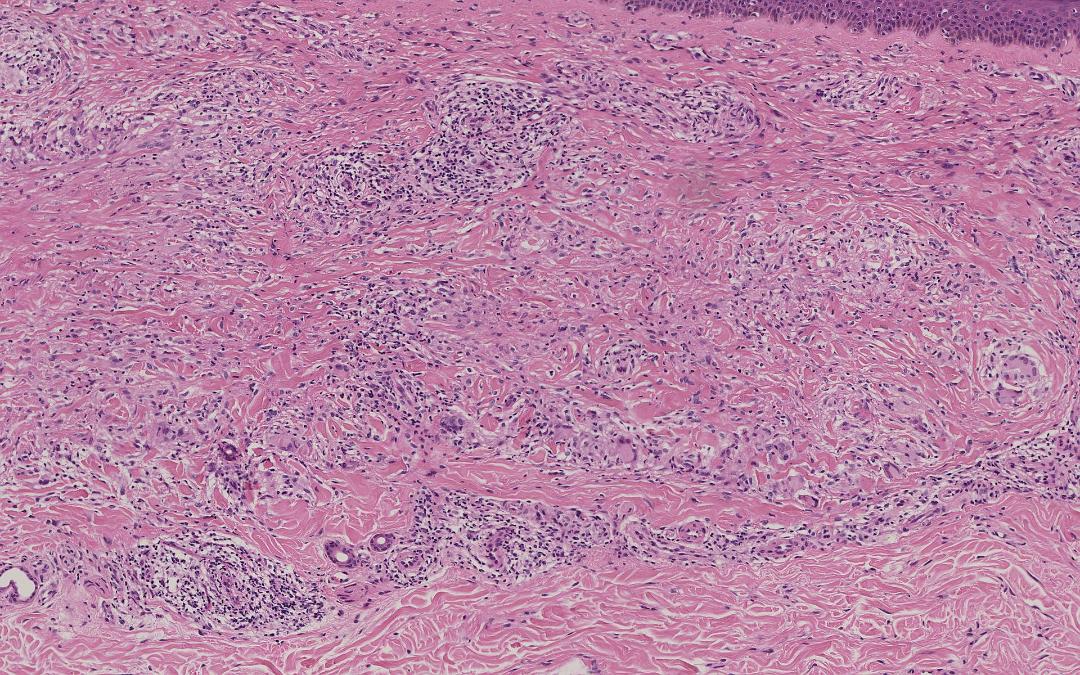

栅栏样模式:特征为真皮中上层淋巴组织细胞炎性浸润,而炎性浸润呈栅栏样包绕胶原及弹性蛋白变性区域。胶原变性区域表现为嗜酸性纤维物质被嗜碱性黏蛋白沉积物所分隔。也可能存在嗜酸性粒细胞。

图:大面积的坏死。该区域被组织细胞和淋巴细胞的外围边缘以及一些多核巨细胞包围。真皮的相邻区域显示正常的胶原束和成纤维细胞核 (HE 40x).

图:右侧为坏死中心,边缘见淋巴细胞和组织细胞,左侧为多核巨细胞(HE 400x).